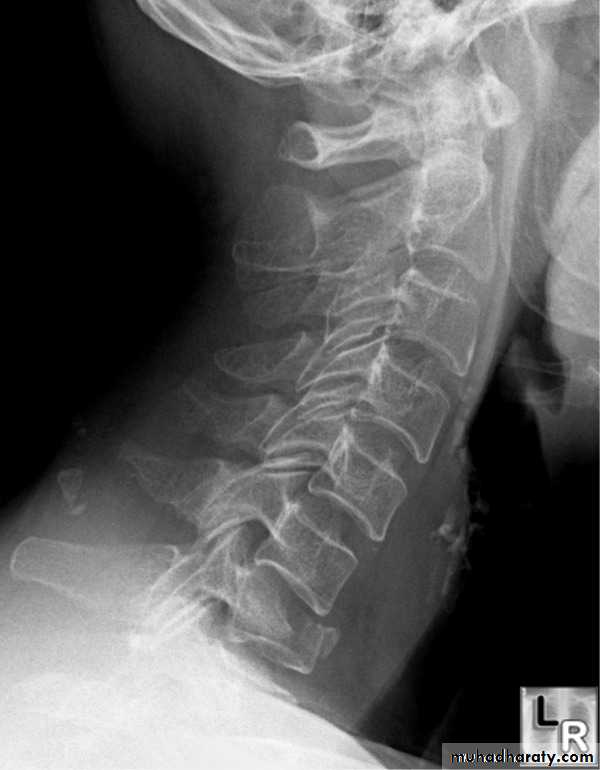

DIAGNOSISX RAY

Anterio posterior X ray radiograph.lateral radiographs with the head in flexion and extension may revealinstability that is not shown in the routine lateral film.

oblique views

at 45° are especially helpfula special projection

through the open mouth.Computed tomography (CT)

and magnetic resonance imaging (MRI).